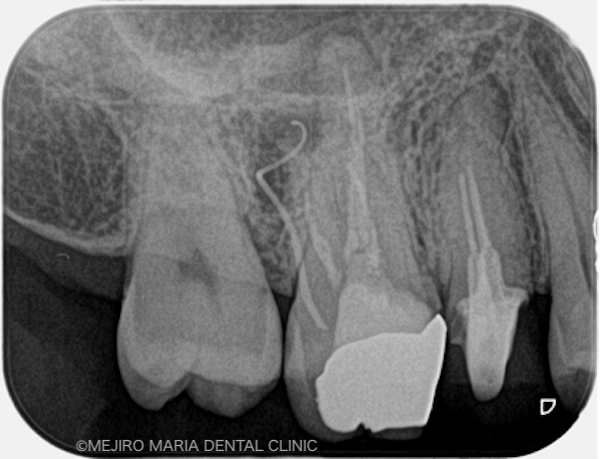

右上6番の歯に確認できたフィステル(瘻孔)は、2回目の根管治療の際にはすでに消失していました。患者様のご希望により、すでに根管治療がされている手前側の歯(右上5番)も、根管治療をやり直すこととなりました。

術後3ヶ月の経過は良好だったため、最終補綴処置を完了し、その後1年間、経過を確認しました。その結果、右上6番の歯に確認できていた病変も消失し、現時点は予後良好と判断しています。